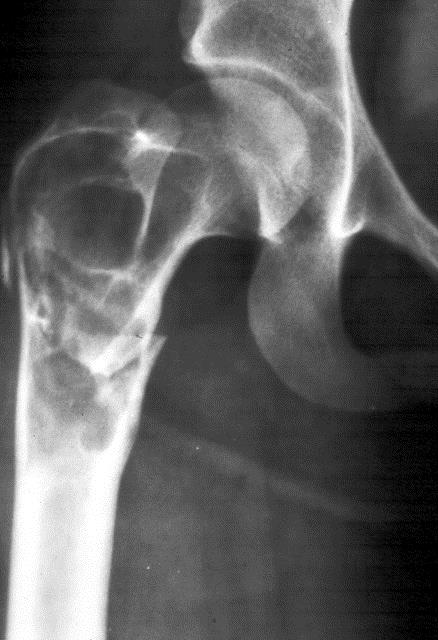

In the pelvis, proximal ends of the femura are commonly involved. Generally it is unilateral (Figure 16). In polyostotic form, involvement of the iliac and other bones is common (Figure 17). Radiologically, the head and neck of the femur are deformed and present a shepherd’s crook deformity (Figure. 18). On occasion, a cystic lesion with multiple loculations is encountered (Figure 19).

Figure 18: FD – 8 yr old child – shepherd crook deformity of femur.

Figure 19: FD – Multiloculated appearance.